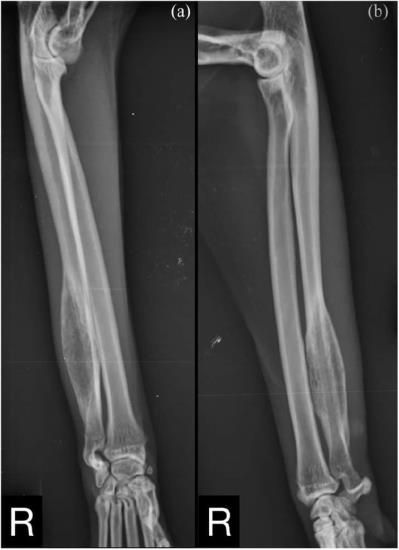

Under general anaesthesia, mediolateral and craniocaudal radiographs of the left and right antebrachium and manus were obtained using a digital radiography system (ACEM Vet Care Raffaello HF30-HF3-/4; Konica Minolta Regius Σ II [54 kVp, 20 mAs]) and a table-top technique.

Radiological evaluation revealed moderate swelling of the soft tissue around the radius and ulna, and a large monostotic ulnar lesion measuring approximatively 40 × 10 mm at the level of the distal diaphysis (Figure 1). This lesion extended distally to the distal ulnar metaphysis, and proximally along the ulnar diaphysis for approximately 40% of its length. There was a short transitional zone between the lesion and the normal bone.

Figure 1 (a) Craniocaudal and (b) mediolateral views of the right antebrachium. A large monostotic lesion is observed on the distal diaphysis of the ulna

The mass had a fusiform shape, with evidence of moth-eaten lysis and cortical expansion. A focal solid periosteal reaction could be seen on the lateral margin of the proximal aspect of the lesion, while a small area of lamellated periosteal reaction was noted on the medial margin. A triangular area of organised subperiosteal new bone (Codman’s triangle) was also evident.